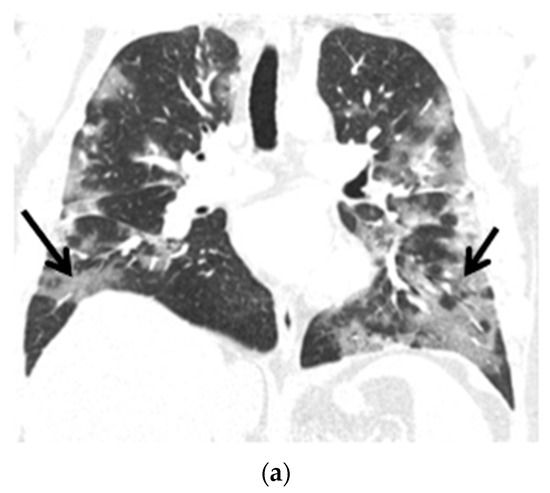

The control chest X-ray showed an almost complete regression of parenchymal lung disease, compared to the initial examination (Figure 1b). A follow-up CTPA showed complete regression of pulmonary embolism (Figure 2a,b); moreover, significant regression of parenchymal lung disease was found (Figure 3a,b).

Figure 3.

(a) Chest CT scans (lung window, coronal view) show patchy ground-glass opacities in accordance with COVID-19 dominant in the peripheral zones of the lower lungs (black arrows); (b) Chest CT scans (lung window, coronal view) after six months of follow-up show resolution of lung lesions (black arrows).